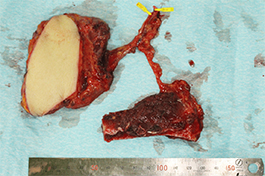

下顎歯肉癌

切除と同時に下顎骨の再建を行います。当科では血管柄付肩甲骨、広背筋の遊離複合皮弁を用いて再建を行うことが多いです。骨再建を行えば、インプラント治療を術後に行うことができ、よりよい咬合再建が可能となります。